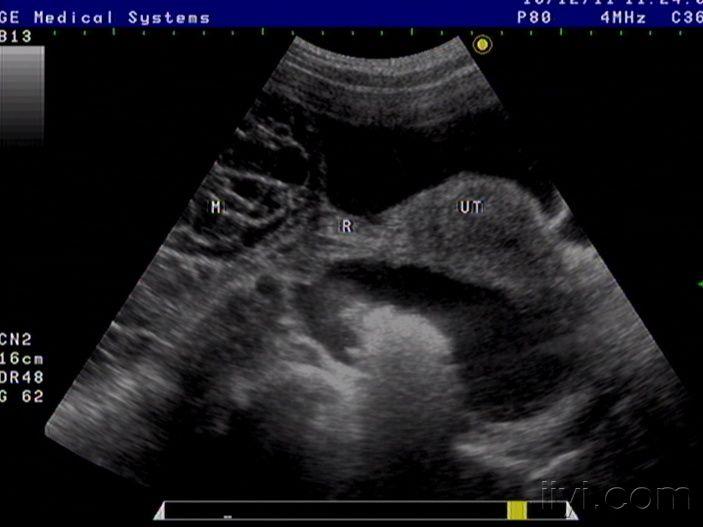

42岁女性患者,自觉腹胀一月余,未诉其它不适,月经规则,彩超中下腹部至盆腔左右各一包块如图,请老师看看像什么,以前没见过这样的这么大的包块

粘液性囊腺癌

是啊,网膜都已经广泛转移了,